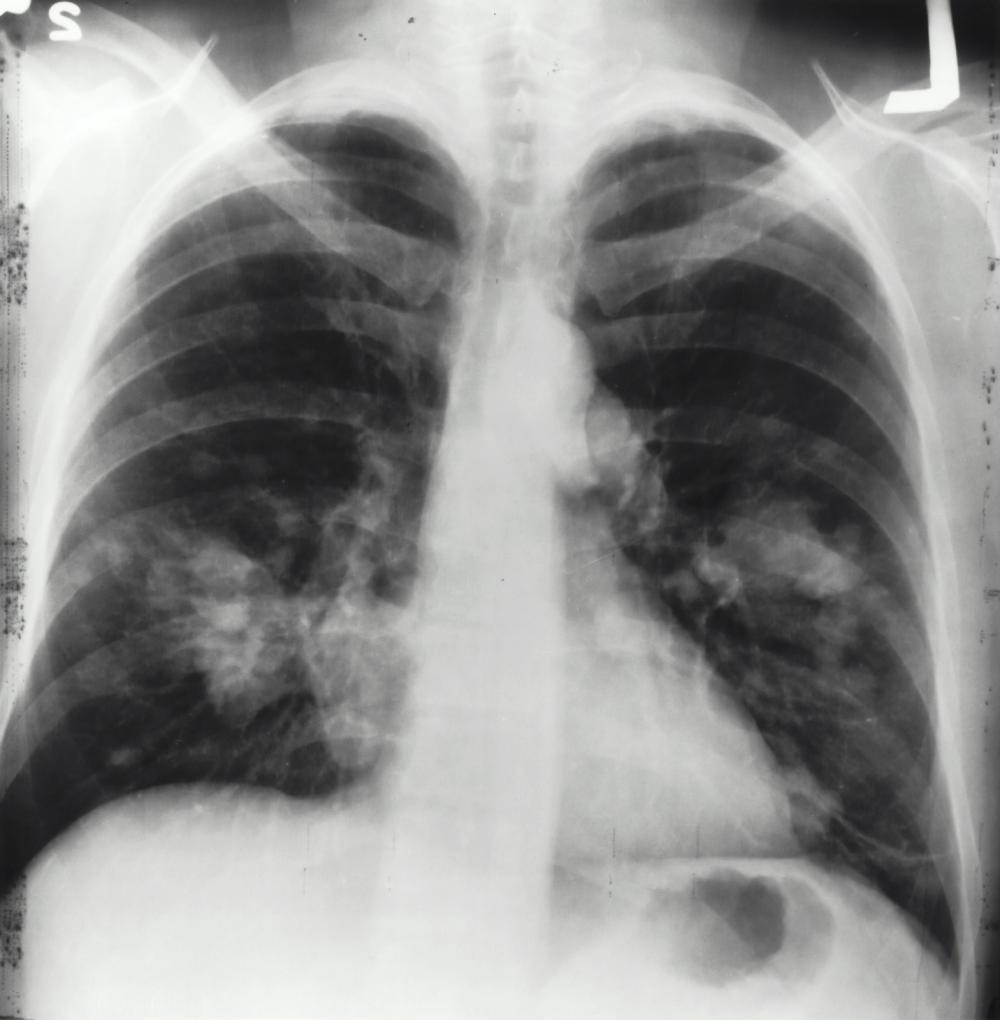

Tubercolosi, in Ue un caso su cinque rimane non diagnosticato

Il Centro europeo per la prevenzione e il controllo delle malattie (Ecdc) e l'Ufficio regionale per l'Europa dell'Organizzazione mondiale della sanità (Oms) hanno pubblicato oggi il rapporto congiunto "Sorveglianza e monitoraggio della tubercolosi in Europa 2026". Il rapporto rivela che la Regione europea, che comprende 53 paesi tra Europa e Asia centrale, inclusi i 30 paesi dell'Unione europea e dello Spazio economico europeo (Ue/See), continua a non raggiungere gli obiettivi regionali e globali per l'eradicazione della tubercolosi su due fronti: una persistente difficoltà di individuazione, con un caso di tubercolosi su cinque non diagnosticato o non segnalato, e livelli di resistenza ai farmaci che rimangono di gran lunga superiori rispetto ad altre regioni. Queste due crisi sono inseparabili. Le persone a cui viene diagnosticata la tubercolosi in fase avanzata hanno maggiori probabilità di trasmetterla ad altri e sono più difficili da curare. Una maggiore trasmissione della tubercolosi può comportare un elevato numero di fallimenti terapeutici, che rappresenta una delle principali cause della resistenza. Colmare il divario nell'individuazione e contrastare la resistenza ai farmaci non sono priorità parallele, ma parte della stessa lotta.